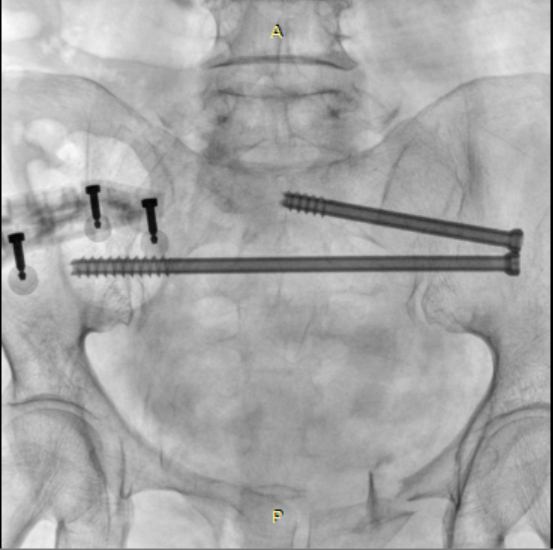

术后骨盆DR片

在手术过程中,骨科手术机器人展现了卓越的性能。通过精确的术前规划和实时的术中导航,医生仅通过几个微小的切口(每个仅1cm长),便成功地置入了2枚骶髂螺钉和4枚骨盆外固定Schanz钉。在骨科手术机器人的辅助下,此次手术时间较传统手术明显缩短,术中失血量仅约20ml,手术创伤小,大大降低了手术风险。值得注意的是,此次手术采用新型的骨盆支架外固定术,该技术可将Schanz钉完全置入髂骨内外板之间并打入髋臼顶相对致密且丰厚的骨质内,使骨盆骨折得到了有效固定,且该技术具有基于触诊、不依赖透视、置钉精准且深入的优势。得益于骨科手术机器人微创手术治疗,该患者在术后3天即顺利出院,体现了现代快速康复理念。骨科手术机器人技术的顺利开展,标志着金瓶梅电影 在数字智能治疗复杂骨盆骨折疾病方面迈入精准微创新高度。